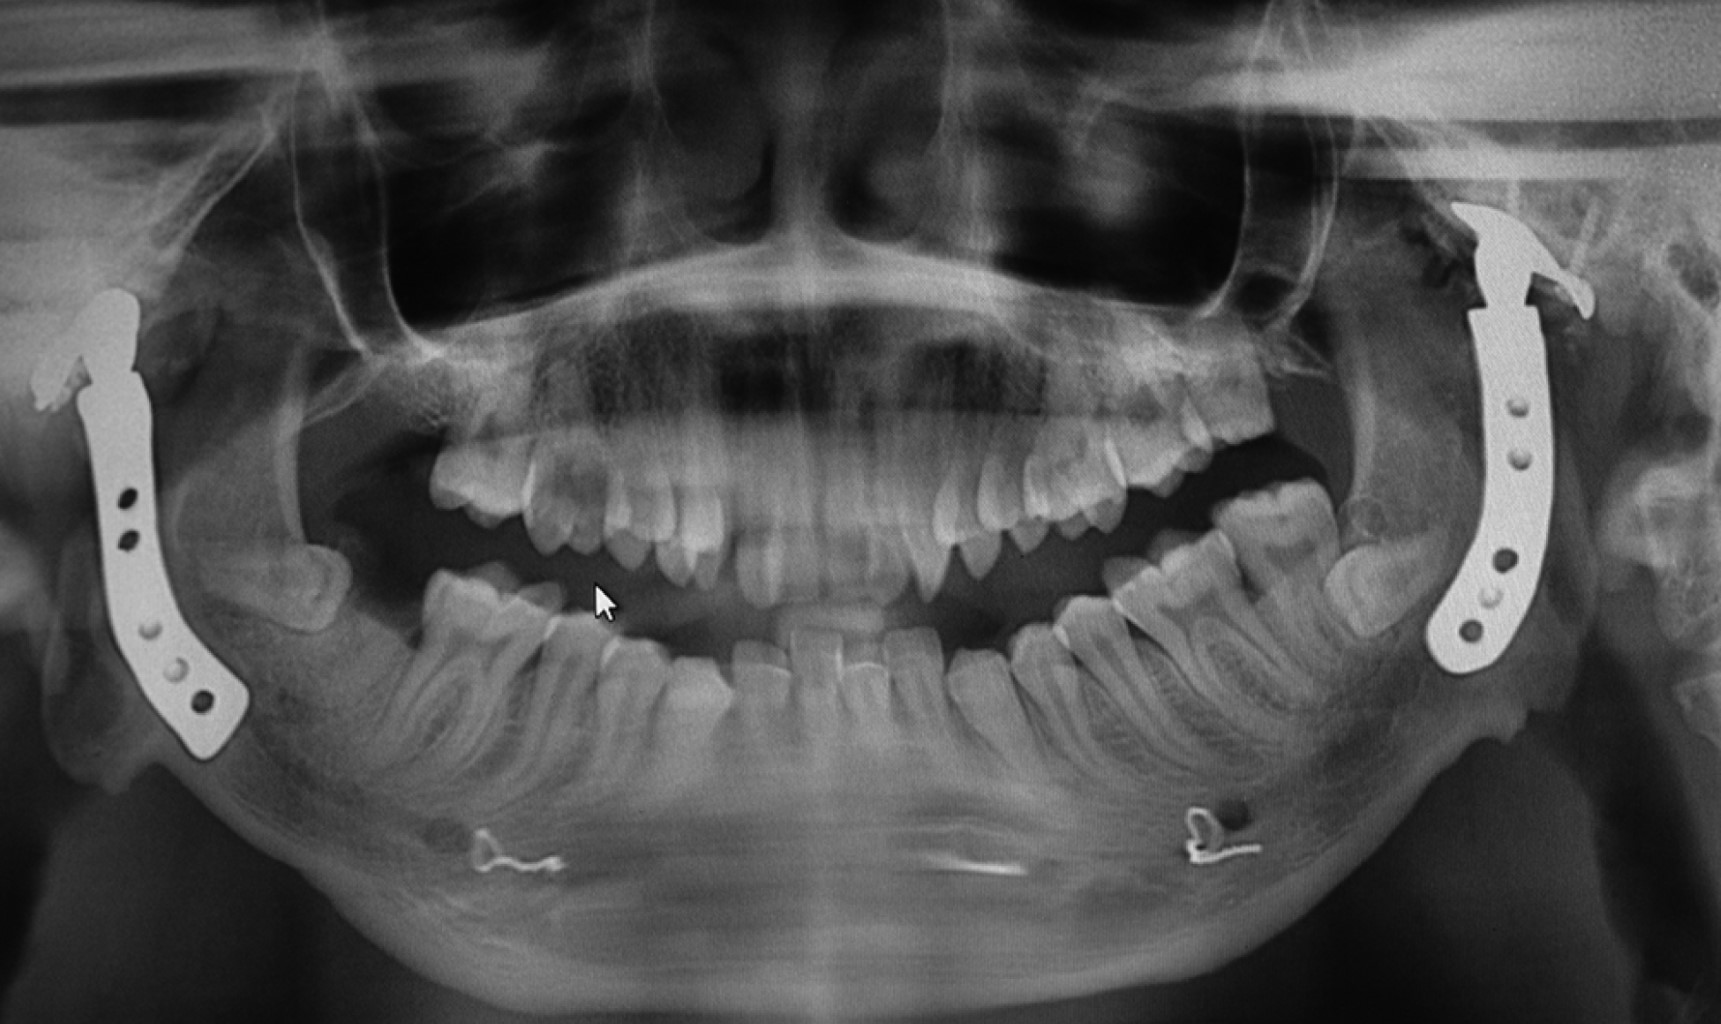

Masculino de nueve años de edad intervenido quirúrgicamente en el año 2005 por presentar anquilosis temporomandibular derecha posterior a trauma facial al caer y golpearse la mandíbula (Figura 7). Nula apertura bucal, sin defecto facial importante (Figura 8). Bajo anestesia general intubación nasal con fibroscopio, se realiza liberación de anquilosis con colocación de prótesis articular metálica de titanio lado derecho, evolucionando a la fecha sin rechazo de prótesis, con excelente apertura bucal y estética facial (Figura 9). Presenta desde la primera intervención quirúrgica, ligera parálisis palpebral, que ha ido mejorando con los años. En el año 2016, se realiza mentoplastia de avance para mejorar la estética facial, se programa para extracción quirúrgica de segundo y tercer molares retenidos. A la fecha sin complicaciones qué reportar en su crecimiento y desarrollo (Figura 10).

Figura 10